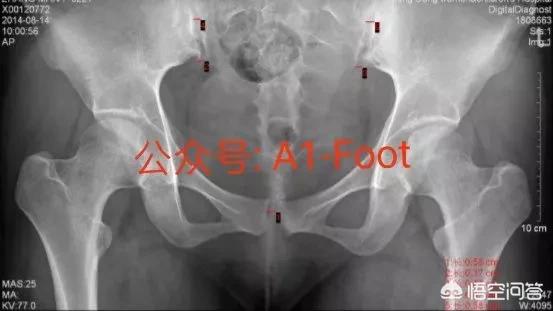

Suivez le numéro public WeChat A1-Foot et lisez l'article scientifique original "Neglected Maternal Pubic Bone Separation Pain".

La "symphyse pubienne" est une complication de la grossesse, une maladie chirurgicale maternelle et une morbidité périnatale. Le taux de prévalence dans les pays étrangers est de 1:300~1:3000, et l'élargissement de la symphyse pubienne se produit au plus tôt vers 10 semaines de grossesse, et atteint son apogée près de la date prévue de l'accouchement. La symphyse pubico-pubienne provoque de fortes douleurs chez les femmes enceintes. Si elle n'est pas traitée à temps, ses symptômes peuvent persister pendant plus de 8 semaines. Pendant le travail, la douleur de la symphyse pubienne peut limiter les mouvements de la femme enceinte, ce qui est préjudiciable à sa santé et au développement intra-utérin du fœtus. Pendant le travail, la progression de l'accouchement est affectée, ce qui entraîne une stagnation du travail et une augmentation du taux de césariennes. La situation s'aggrave dans la période post-partum, affectant la récupération du corps de la mère, limitant ses mouvements et, dans les cas les plus graves, provoquant une incontinence urinaire, des fuites urinaires et un prolapsus utérin, tout en la rendant facilement agitée et déprimée, ce qui accroît l'incidence de la dépression post-partum.

Diagnostic de la symphyse pubienne séparée :

① douleur sévère de la symphyse pubienne maternelle prénatale ou postnatale, activité, retournement en cas d'aggravation, peut être associée à une douleur lombosacrée et des membres inférieurs ; ② quelques difficultés à marcher, démarche en canard ; ③ une partie du patient est apparue dans le dos lombaire, douleur inguinale ; ④ examen physique la symphyse pubienne sont une pression et une douleur évidentes, la compression pelvienne - test de séparation est positive, peut être touchée pour élargir l'écart de la symphyse pubienne ; ⑤ échographie prénatale ou DR et CT postnatale montrent que la largeur de la surface de séparation de la symphyse pubienne est supérieure à 10 mm. L'échographie prénatale ou la radiographie et la tomodensitométrie postnatales ont montré que la symphyse pubienne était séparée et que la largeur de la surface séparée était supérieure à 10 mm.

La patiente suivante, qui souffrait d'une séparation post-partum de l'os pubien, a été stabilisée et s'est rétablie avec succès après un repositionnement manipulatif précoce et une fixation externe à l'aide d'une bande pelvienne croisée.